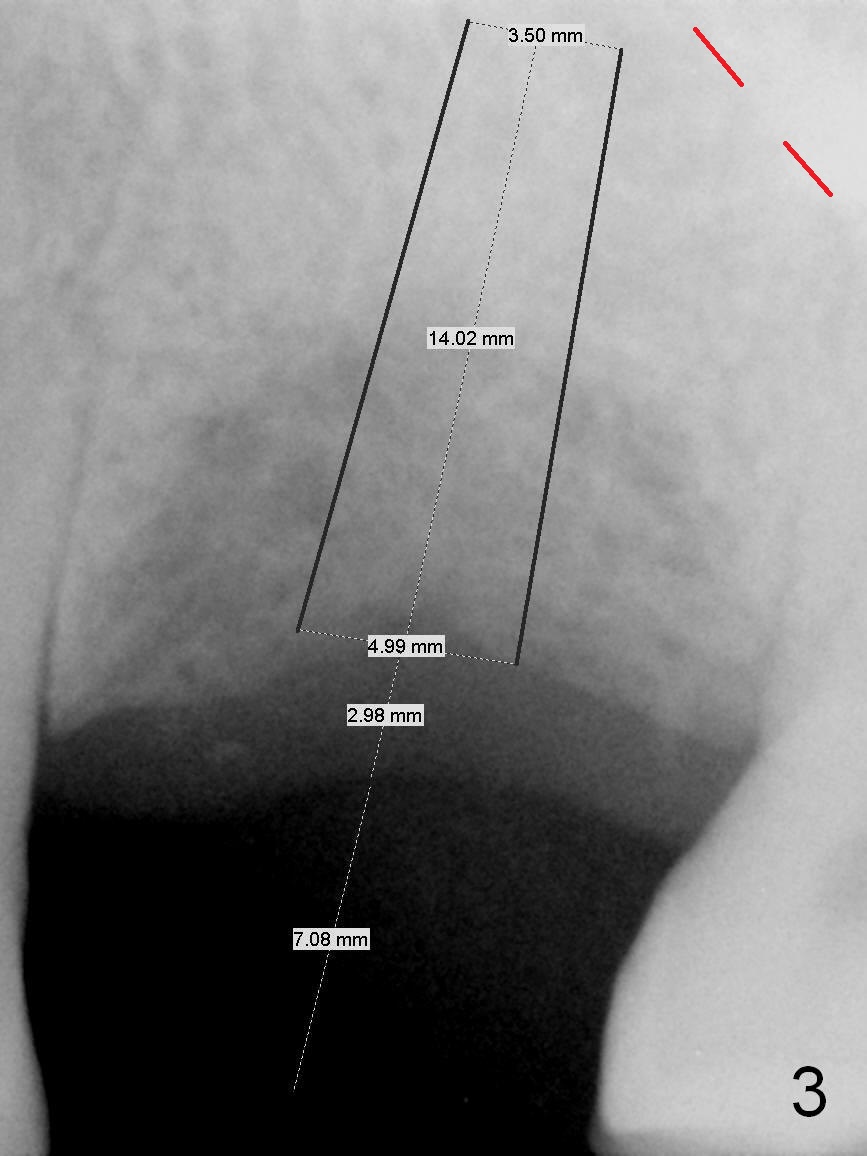

The tooth #14 of a 52-year-old lady had severe bone resorption 6 years ago (Fig.1 (red dashed line: sinus floor)). The bone resorption persists after the tooth exfoliated (Fig.2). Clinically, the buccal plate (Fig.4 (occlusal view) upper panel: B) is concave (take preop photos). #15 scalpel will be used for incision (red line in Fig.4 lower panel, near the lingual plate (L)) and initiation of bone expansion. The latter is followed by bone scalpels, bone blades and RTs at the depth of 14 mm. A 4.5x17 mm Tatum tapered tap is used for 14 mm. PA is taken. If the bone is dense, the depth is less than 14 mm in bone. Use RT2,3 to reach 17 mm. A 5x14 mm bone-level implant is placed (Fig.3). Crown cementation will be done for the tooth #3 before surgery.